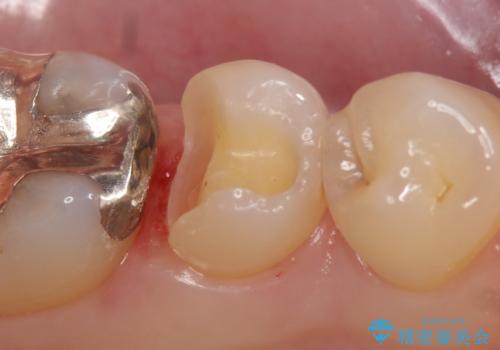

- 他院にて左下5の虫歯治療を行おうとしたところ、歯の神経治療をすると言われたため、できれば神経を残せないかと当院にいらっしゃった方の症例です。

自発痛・持続痛等の症状がなく、露髄(歯の神経が露出してしまうこと)することなく虫歯の除去を完了したため、しばらく経過観察を行った後に神経治療をすることなく、セラミックインレーによる修復を行うことができました。

当院のセラミックインレーはemaxという強度と審美性に優れた材料を使用しています。

またプレス方式でインレーを製作しているため、削り出しで製作するCADCAMより優れた適合性も持ち合わせており、虫歯が再発しにくい修復物です。